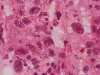

The volume of tissue received for examination amount to an aggregate of 4.0 x 2.0 x 1.5 cm in combined size. Grossly, the tissue is soft and has a creamy color with hemorrhage. The intraoperative cytologic preparation demonstrate a neoplasm composed with small to medium sized blue cells that smear out rather homgeneously and evenly. If you pay attention, there are some larger cells with a substantial amount of cytoplasm even at low magnification (Panel A). On high magnification, the nuclei are rather uniformly large, with high grade of pleomorphism, and almost all cells contain a distinct nucleoli. Apoptotic bodies and mitoses are frequent (Panel B). There are also large cells with prominent nucleoli and substantial amount of eosinophilic cytoplasm. These cells are suggestive of rhabdoid cells but none of them have the distinct inclusion body like cytoplasmic eosinophilic body of the rhabodid cells in atypical teratoid rhabodid tumor (Panel C). In the frozen section, both small to medium sized cells and cells with large nuclei with large, prominent, and eosinophilic nucleoli (Panel D and E). In the permanent sections, there is extensive necrosis (Panel F). The histology is in general agreement with that of frozen section except that the tumor cells appear to have more cytoplasm and more plemorphic, large nuclei with prominent nucleoli in comparison to the frozen section (Panel G). Large cells with substantial volume of cytoplasm, large, bizarre nucleoli and prominent, eosinophilic nucleoli are also noted (Panel H). There is a generalized degree of high grade pleomorphism. Results of immunohistochemistry are as follow:

Comment: This is an interesting case. Histologically, the overall morphology is consistent with a medulloblastoma with high grade of pleomorphism. Therefore, a diagnosis of large cell (anaplastic) medulloblastoma is the most likely diagnosis. The problem is the large cells with substantial amount of cytoplasm and large bizarre, eccentric nuclei with large nucleoli. These features raise the possibility of an atypical teratoid rhabdoid tumor (ATRT). These cells, if you observe carefully, lack the cytoplasmic, eosinophilic, inclusion body typical for rhabdoid cells. Nuclear wrapping is not readily seen. In fact, we did not find unmistakable nuclear wrapping until we looked at the immunohistochemistry for neurofilament. There are three immunohistochemical features in this case that are against a diagnosis of ATRT. First, vimentin is typically positive in most, if not all, tumor cells particularly those cells with rhabdoid changes. Second, most ATRT are positive for EMA. Third, the most powerful proof is the positive immunoreactivity of BAF47 which would be negative in ATRT. The negative result for desmin is helpful in ruling out the possibility of a rhabdomyosarcoma.

Large cell and anaplastic medulloblastomas are recognized as different variants in the new WHO classficiation 1. They share many basic features with medulloblastoma 2, 3. The most notable differences are large cell size, increased variation of nuclear size, prominent and even eosinophilic nucleoli, increased mitotic figures and number of pyknotic or apoptotic cells, and extensive, geographic areas of necrosis. In the experience of the authors, most of the tumor cells in large cell and anaplastic medulloblastomas have high nuclear to cytoplasmic ratio in a manner similar to that of the classic variant. As per the new WHO classification, large cell medulloblastomas are composed mainly of large cells with more cytoplasm than the classic variant or the anaplastic variant. In the experience of the authors, this distinction is not always possible. The case being illustrated here includes some large cells with substantial amount of cytoplasm and but these cells only represent a portion of the tumor cell population. In general, anaplastic and large cell medulloblastomas have less favorable prognosis than the classic variant of medulloblastoma. However anaplastic changes are uncommon and does not affect the prognosis in adult cases as per one study 4.